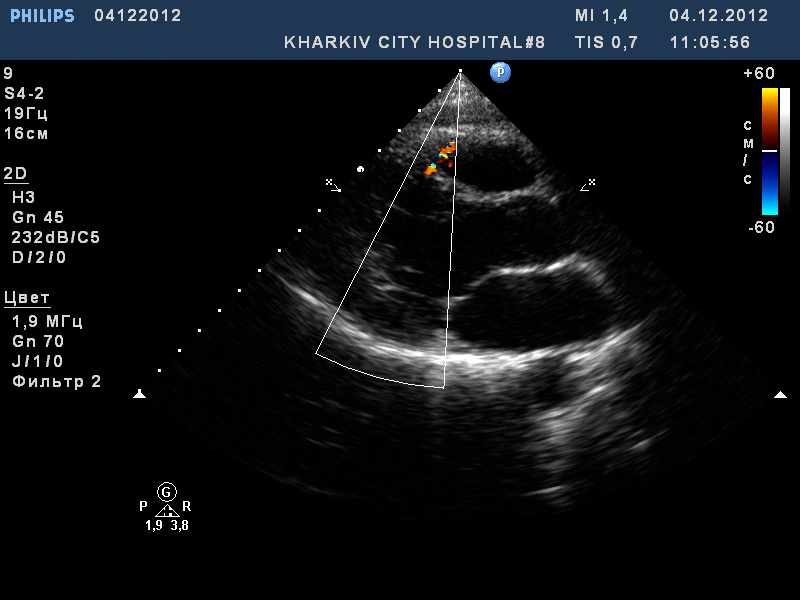

Пациент 23 года.

Дефект МЖП со сбросом слева-напрво, шириною потока до 4,0мм.

Мышечная часть и гемодинамически незначимый? (сорри, плохо знаю эхокардиографию)

Дефекты в мышечной части как правило гемодинамически незначимые, так как не приводят к значительному повышению давления в правом желудочке. "Много слышно, мало видно" - это про них. Ширина потока как правило оказывается больше реального диаметра дефекта.